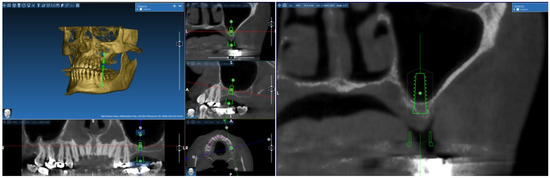

2.1. Digital Modeling

- Generation of the geometric model for CFD numerical analysis from the CBCT image.